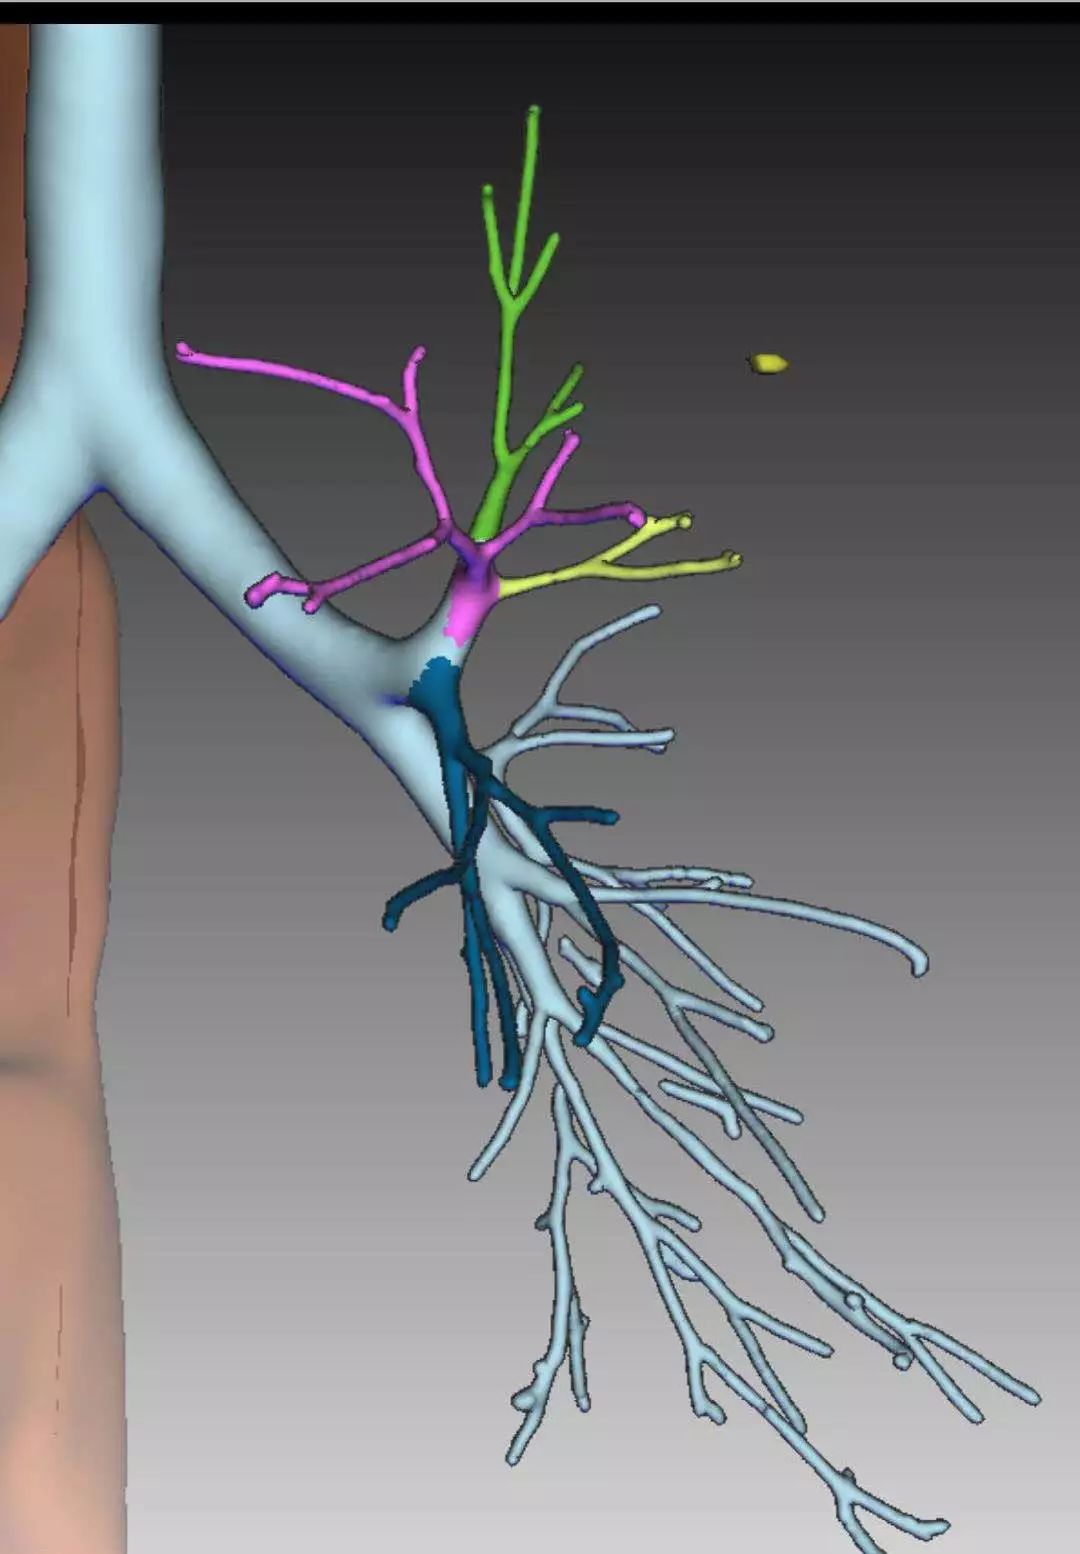

将平面的影像学检查图像重建成3D数字模型

将平面的影像学检查图像重建成3D数字模型DBL帝国网站管理系统